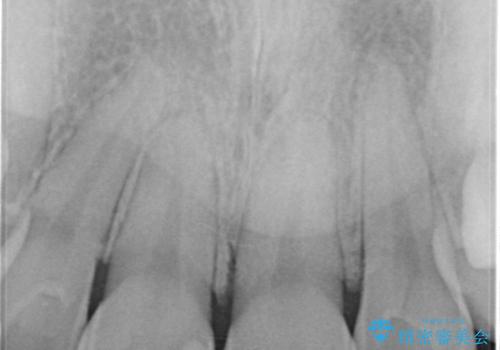

- プラスチックで治療している前歯が何度も欠けてしまうとお悩みで来院された方です。

歯全体を覆うクラウンにて治療を行いました。

前歯1本のみの被せ物治療を行う場合、他の歯を参考に歯の色や形を忠実に再現することが重要です。オールセラミッククラウン(スペシャル・エクセレント)は、事前に歯科技工士との打ち合わせを行うことで、歯の色や形、さらには患者様のご希望も聴取したうえでクラウンを作製することが可能です。